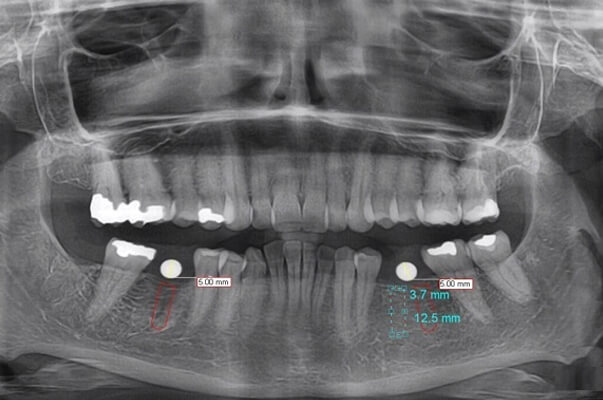

Dental X-rays are images of your teeth that your dental specialist uses to evaluate your oral hygiene. These X-rays are utilized with low degrees of radiation to take image of your teeth and gums interior. This can assist your dental specialist in identifying issues, such as cavities, tooth decay, and affected teeth.